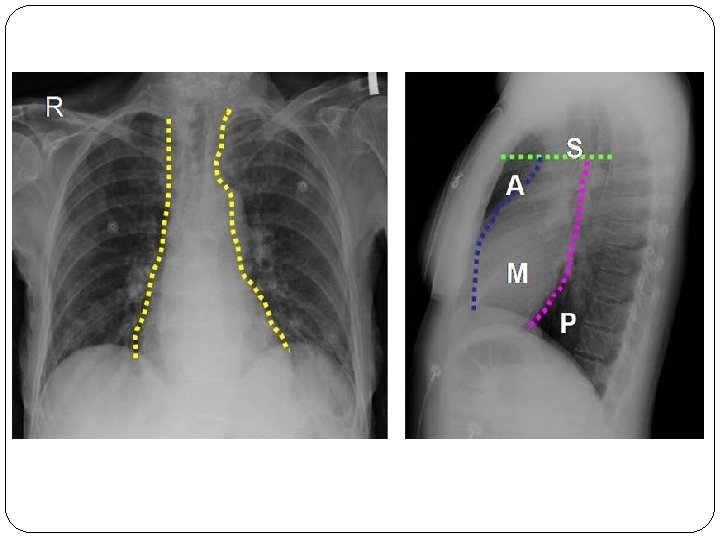

Size & Location of Heart Average Size of Heart • 14 cm long • 9 cm wide • posterior to sternum • medial to lungs • anterior to vertebral column • base lies beneath 2 nd rib • apex at 5 th intercostal space • lies upon diaphragm

The Location of the Heart within the Thoracic Cavity Figure 20. 2 a, b